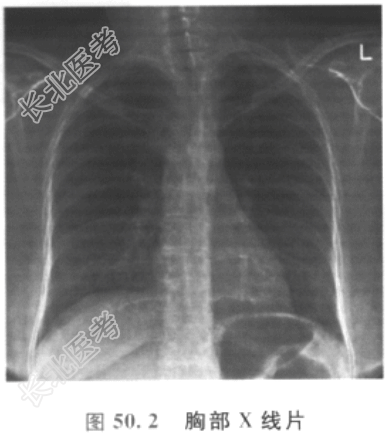

胸部X线片如图50.2所示